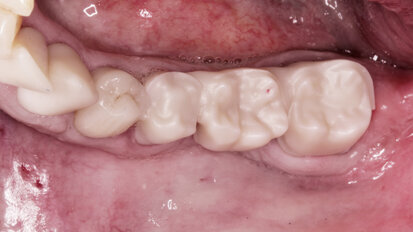

Rehabilitace Straumann